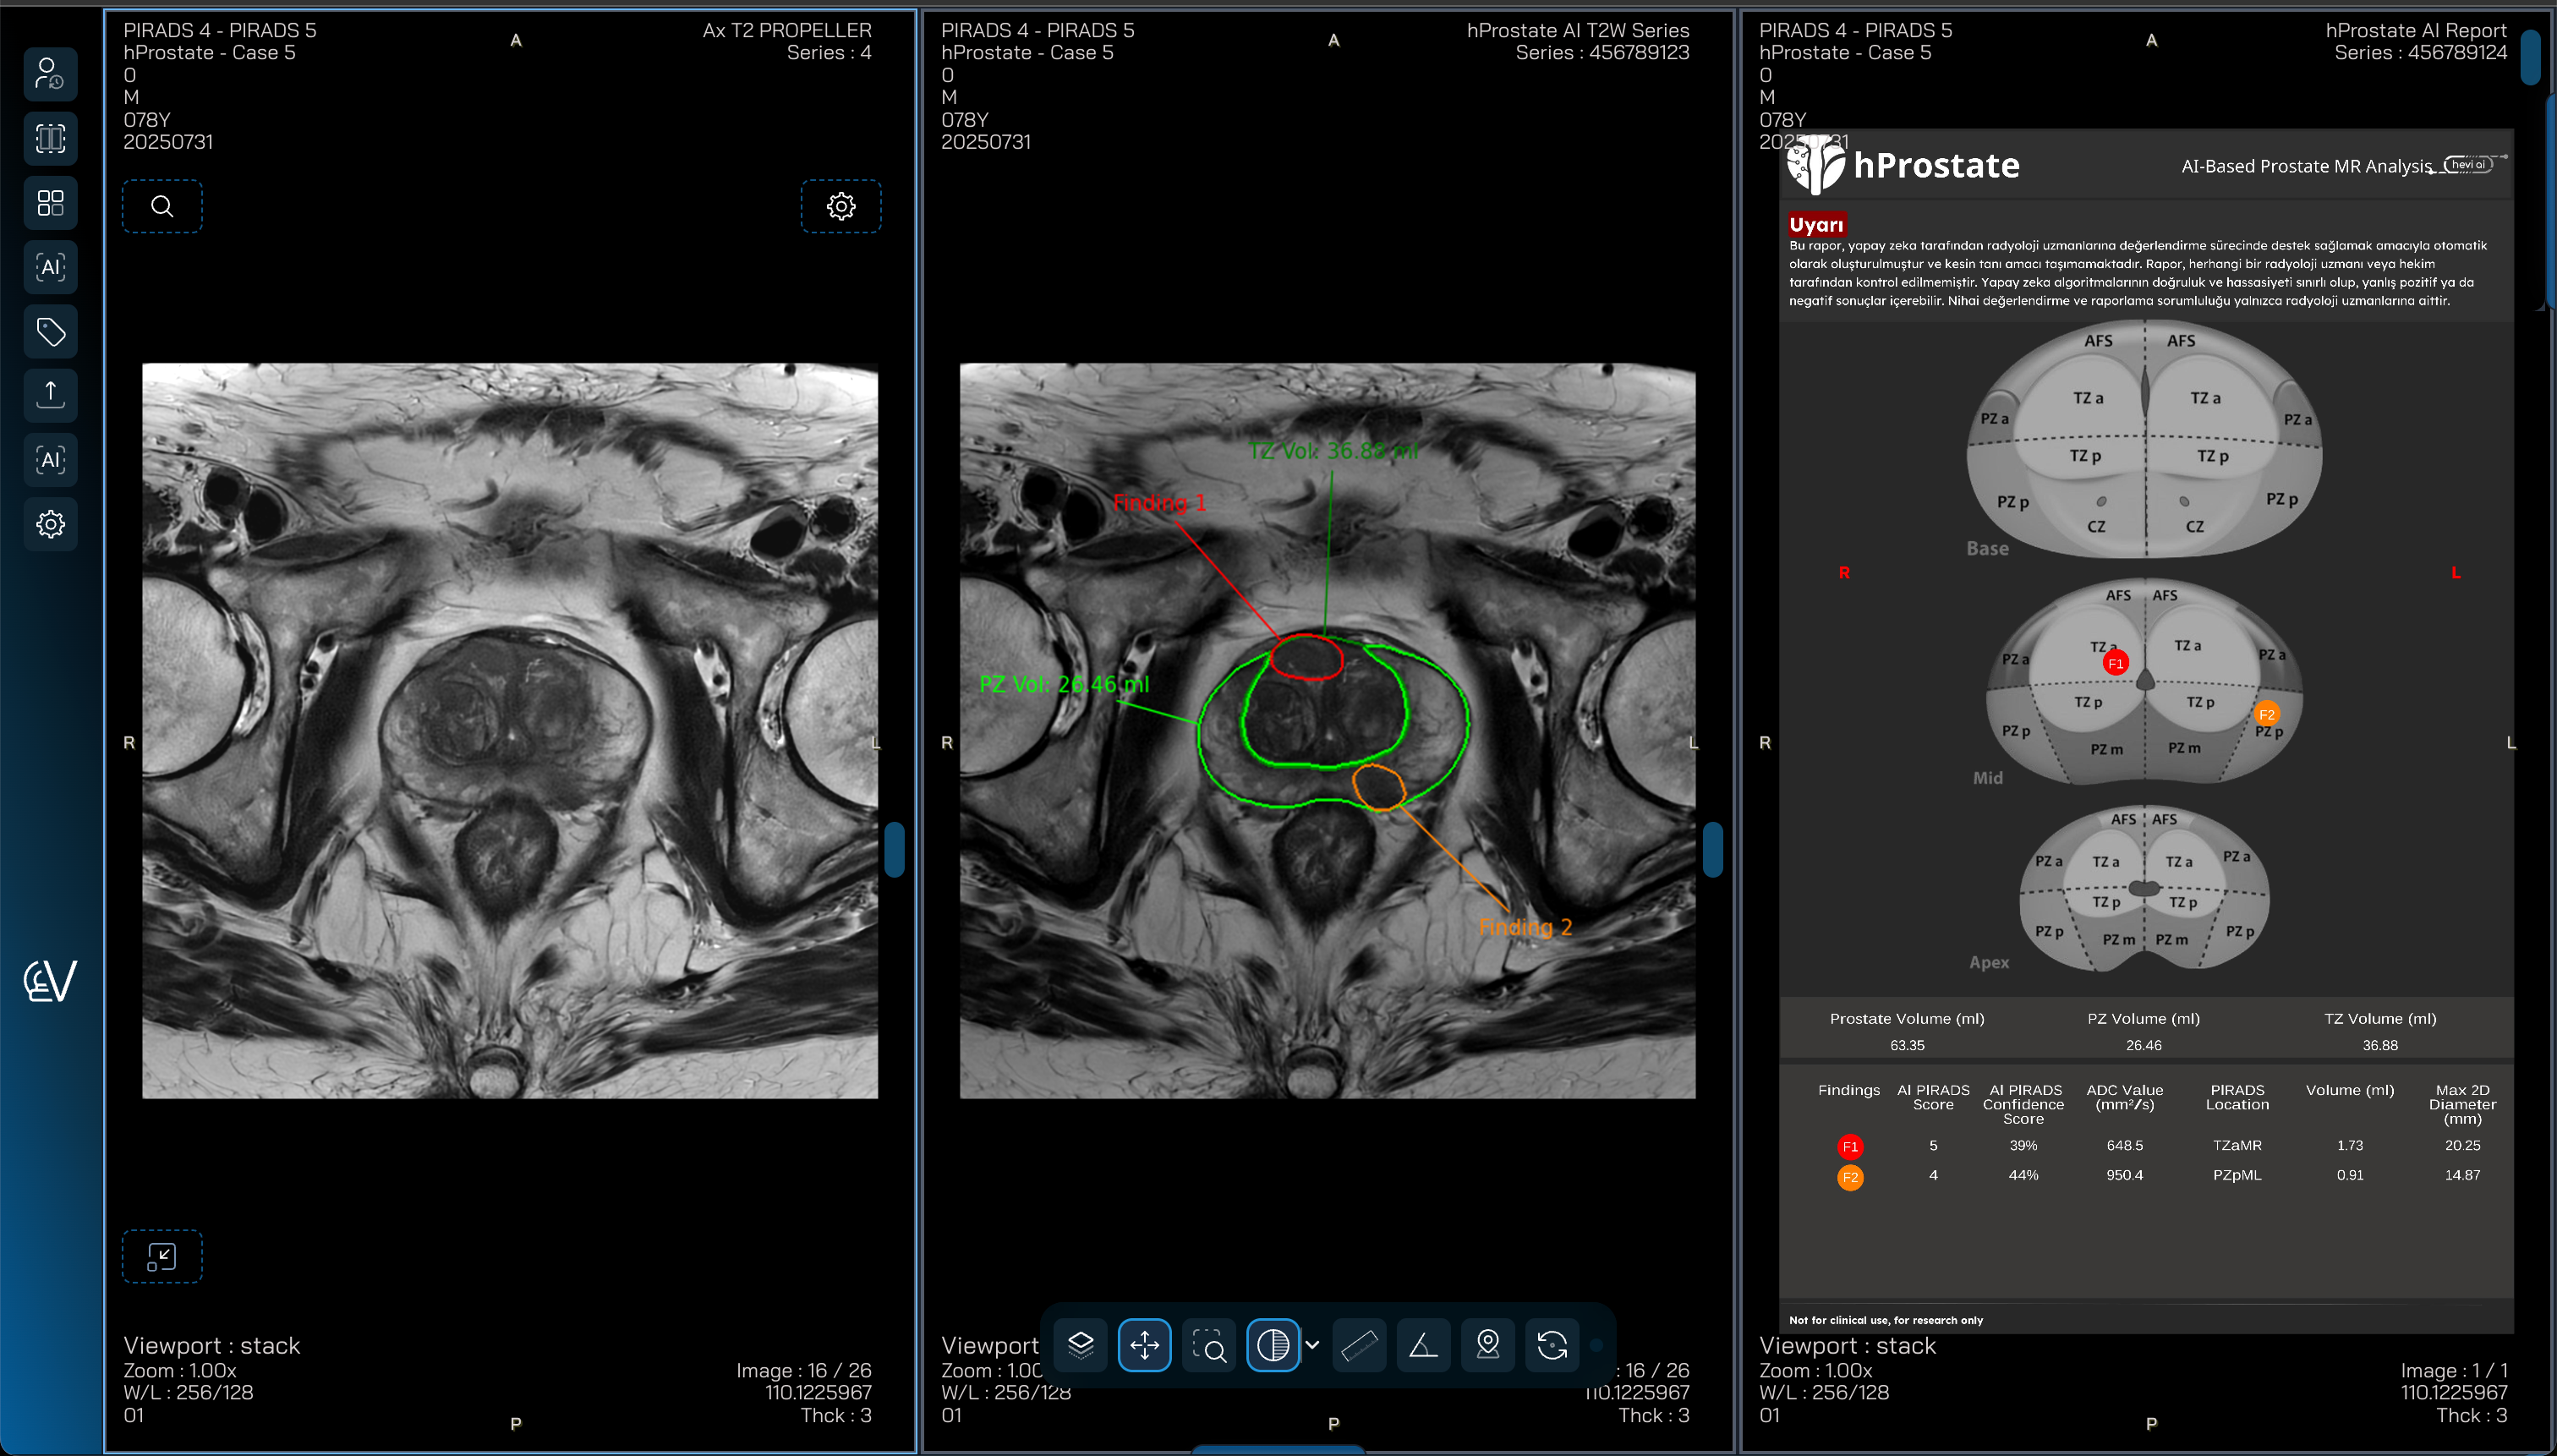

Hevi AI - hProstate

hProstate is an AI-powered clinical decision support solution that analyzes prostate MRI to automatically identify suspicious lesions, support PI-RADS assessment, and assist clinicians in improving accuracy and confidence in prostate cancer diagnosis.